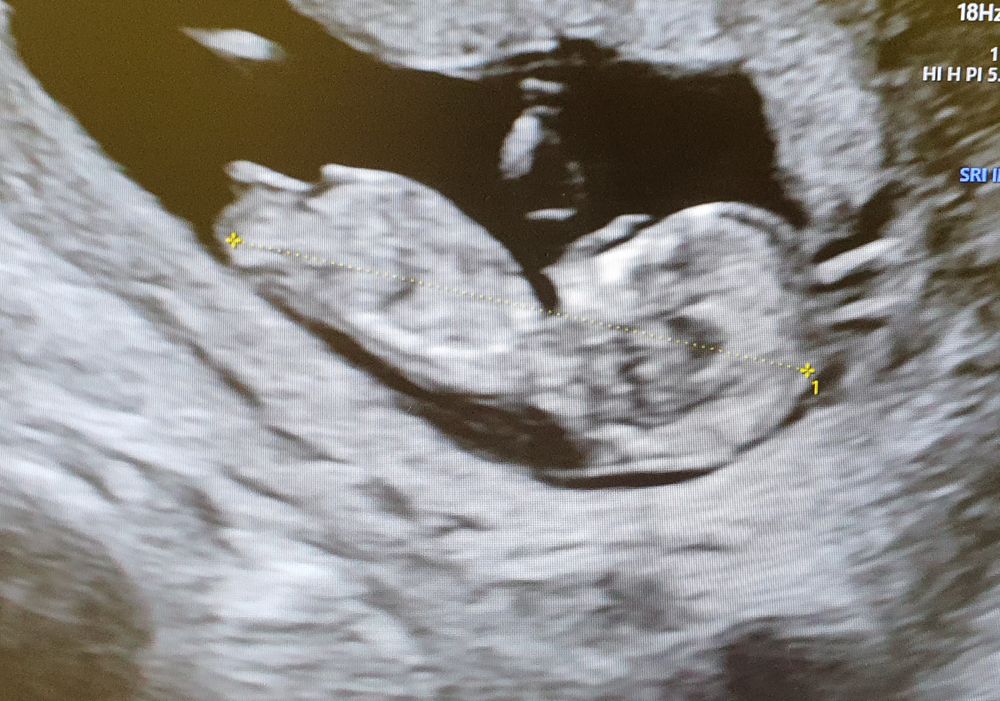

Если эта палочка - половой бугорок, то да, девочка.

Алёна, на этом фото бугорок не видно.

Юлия Sonnце, видно))) сквозь ножку просвечивает

Валерия, нет. Мне надо, чтобы было точно видно. Я вижу только ногу, а через неё, что угодно можно нафантазировать😊 Бугорок мне лично не виден на данном фото.

Изображение Вот «моя девочка» на 1 скрининге пару недель назад )Я если честно не понимаю в этом ,но Пятых на 99,9% уверена ,что девочка )